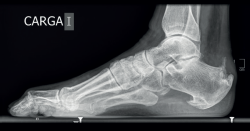

Figura 5. Radiografía lateral en carga del paciente de la Figura 4: obsérvese la ocupación del triángulo de Kager, la presencia de espolones óseos y de una calcificación intratendinosa. Se aprecia también el aumento del espesor de la sombra del tendón de Aquiles, demostrativo del engrosamiento tendinoso y el espolón plantar expresión de la alteración del sistema aquíleo calcáneo plantar.